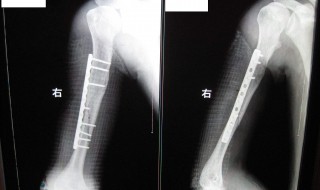

1、工伤骨折两个钢钉算十级伤残。